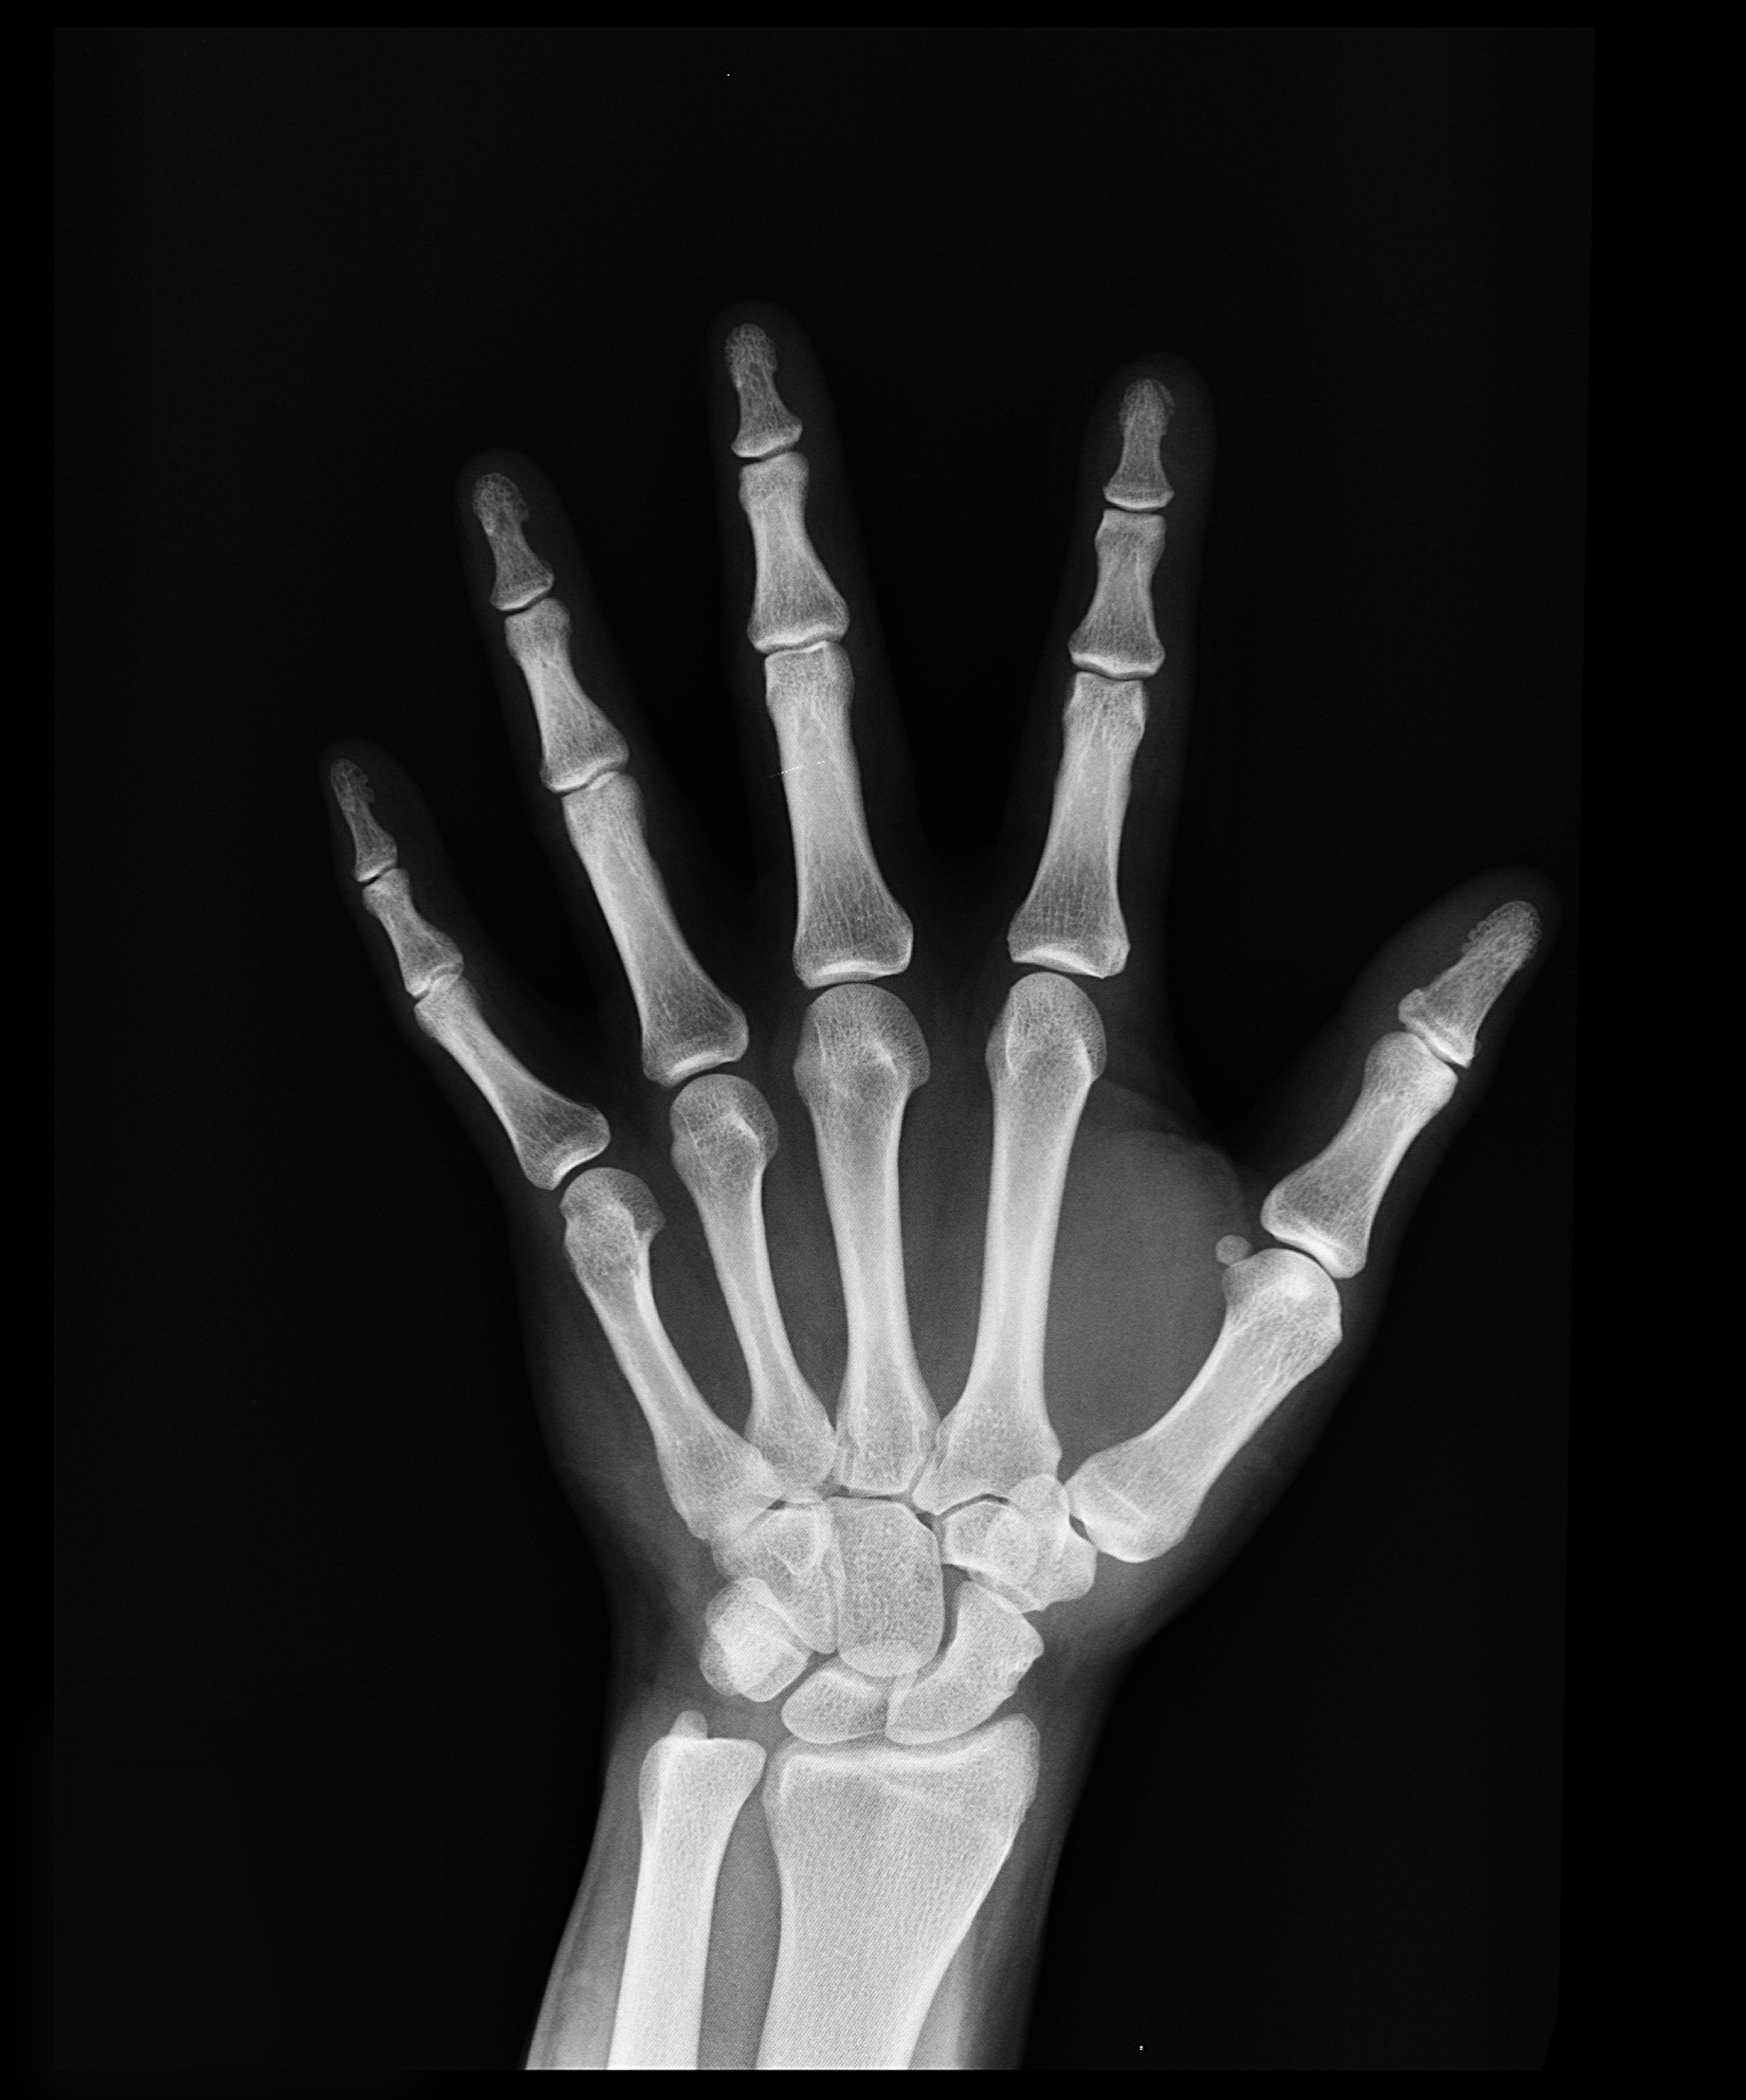

특별한 증상이 없어서 초기에 골다공증을 확인하는 것이 어려운 일입니다. 골밀도가 낮아지면서 허리통증이나 키의 감소와 같은 미묘한 변화가 서서히 나타날 수 있습니다. 하지만 이러한 증상이 나타날 때쯤에는 이미 골다공증이 상당히 진행되었을 수 있습니다. 이는 정확한 진단을 위한 정기적인 건강검진과 전문적인 검사의 중요성을 강조합니다. 의료 전문가들은 뼈 건강을 평가하기 위해 일반적으로 엑스레이와 혈액 검사를 사용합니다. 이러한 진단 도구들은 의료 제공자들이 골다공증의 정도를 결정하고 적절한 치료 계획을 수립할 수 있도록 하면서 골밀도에 대한 귀중한 통찰력을 제공합니다. 조기 발견은 특히 고위험군에 있는 개인들에게 일상적인 건강 검진의 필요성을 강조하면서 골다공증을 효과적으로 관리하는 핵심 요소로 남아 있습니다.